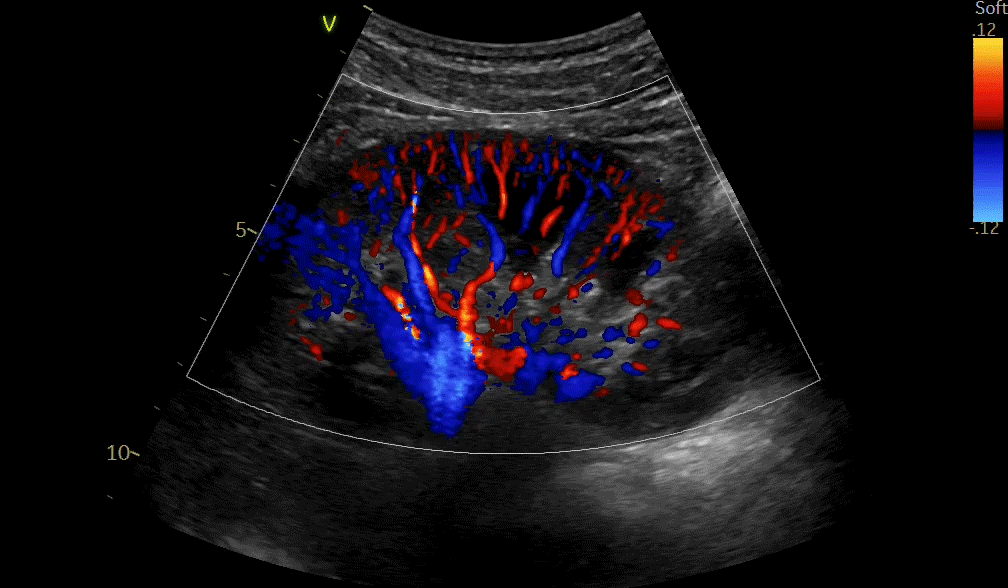

4D color imaging with the 4Vc-D probe

4D TEE color imaging with Vmax

10T-D Color Flow